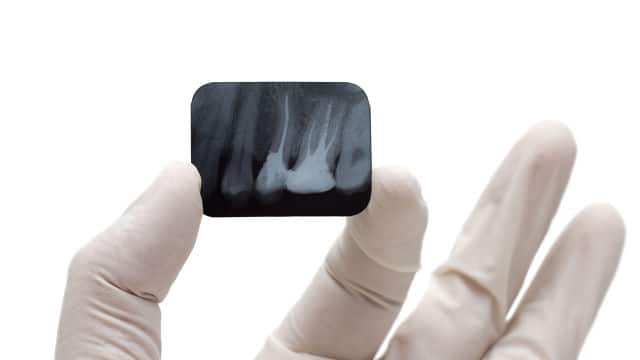

X-Rays

Oral And Maxillofacial Radiology: The Dental Specialty Dedicated To X-Rays

X-rays are an important part of your dental visit, and there's a whole specialty dedicated to them called oral and maxillofacial radiology. Here's more.

X-Rays

X-Rays for Children

Children's mouths should be x-rays in accordance with your child's development and dental health. Find out more about dental x-rays for children, here.